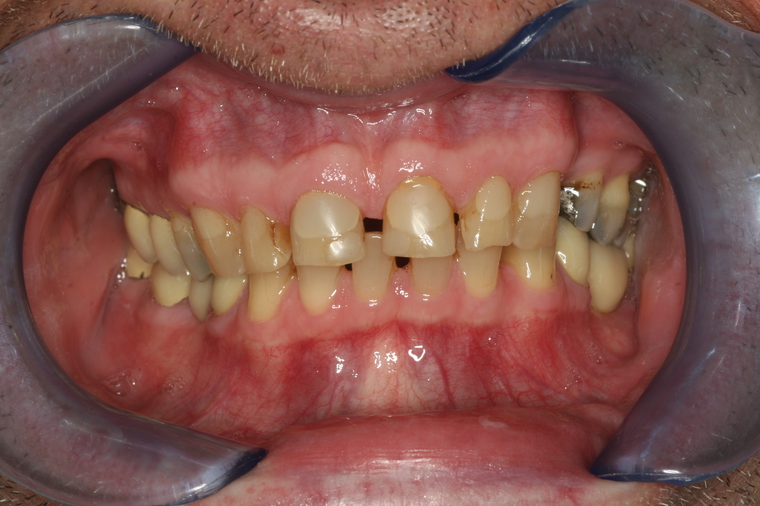

Generalsanierung

Viele Kunden die zu uns nach Salzburg kommen benötigen eine Generalsanierung der Zähne. Gründe dafür sind Zahnarztangst, Zeitmangel und schlechte Erfahrungen in der Kindheit. Unser Konzept ist genau auf diese umfangreichen Fälle abgestimmt:

Bei einer Generalsanierung müssen alle zahnmedizinischen Bereich in Betracht gezogen werden, dies beginnt bei der Aufklärung und Prophylaxe, gefolgt von Zahnfleischbehandlungen und Kariestherapie, eventuellen Zahnentfernungen, Knochenaufbauten und wird durch ästhetischen Zahnersatz abgeschlossen. Unser Recall-System hält die erreichte Zahnsanierung über lange Jahre stabil.